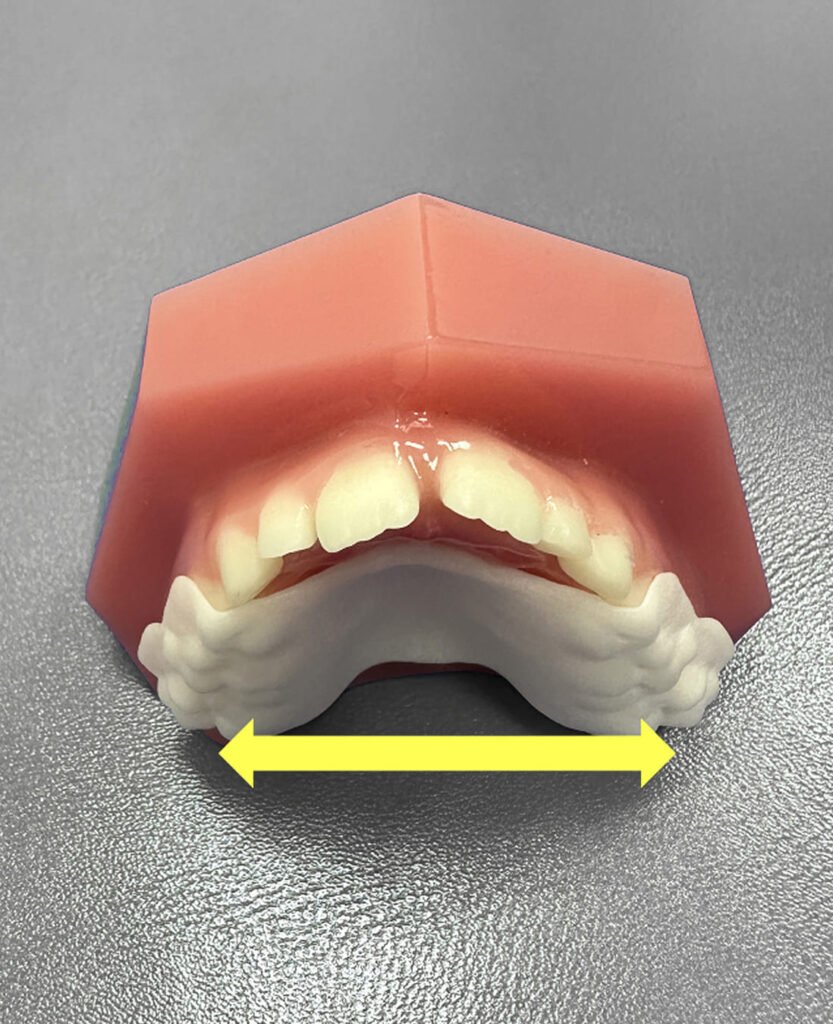

Tratamientos para guiar el crecimiento dental

Realizar controles tempranos permite detectar alteraciones a tiempo y evitar tratamientos complejos más adelante.

Durante las primeras consultas de ortodoncia infantil analizamos cómo se desarrolla la dentición y decidimos la mejor manera de acompañar el recambio dental natural. Lo ideal es comenzar con las revisiones a partir de los 3 años.